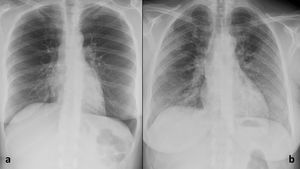

En general, hubo una disminución del número de diferencias estadísticamente significativas (DESRD) entre el grupo de estudiantes y el de residentes y radiólogos en la primera evaluación (21 DESRD [66,66%]) y la segunda (17 DESRD [58,33%]), así como en la evaluación con IA (15 DESRD [45,83%], fig. 7).

Comparación del rendimiento diagnóstico para la primera y la segunda evaluación, y para la evaluación con inteligencia artificial (IA).

Para cada evaluación, el área bajo la curva (AUC) corresponde al centro de la barra y sus intervalos de confianza del 95% a los límites de la barra. Las flechas representan las diferencias significativas según la prueba de DeLong de cada estudiante de medicina con el resto de los lectores. El número de diferencias significativas disminuye entre la primera y la segunda evaluación, y entre la segunda y la evaluación con IA. No hubo diferencias significativas entre radiólogos residentes, radiólogos expertos o entre residentes y expertos en las evaluaciones primera, segunda y con IA.

IA: inteligencia artificial; EM4-1: estudiante de medicina de cuarto año número 1; EM4-2: estudiante de medicina de cuarto año número 2; EM5-1: estudiante de medicina de quinto año número 1; EM5-2: estudiante de medicina de quinto año número 2; EM6-1: estudiante de medicina de sexto año número 1; EM6-2: estudiante de medicina de sexto año número 2; RR2: residente de radiología de segundo año; RR3: residente de radiología de tercer año; RE1: radiólogo experto número 1; RE2: radiólogo experto número 2.